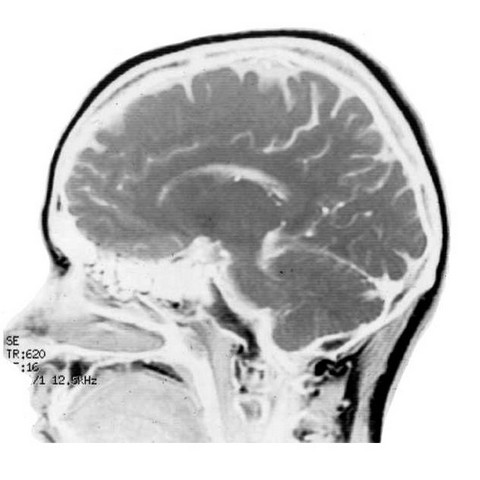

Neurología de la música y del lenguaje